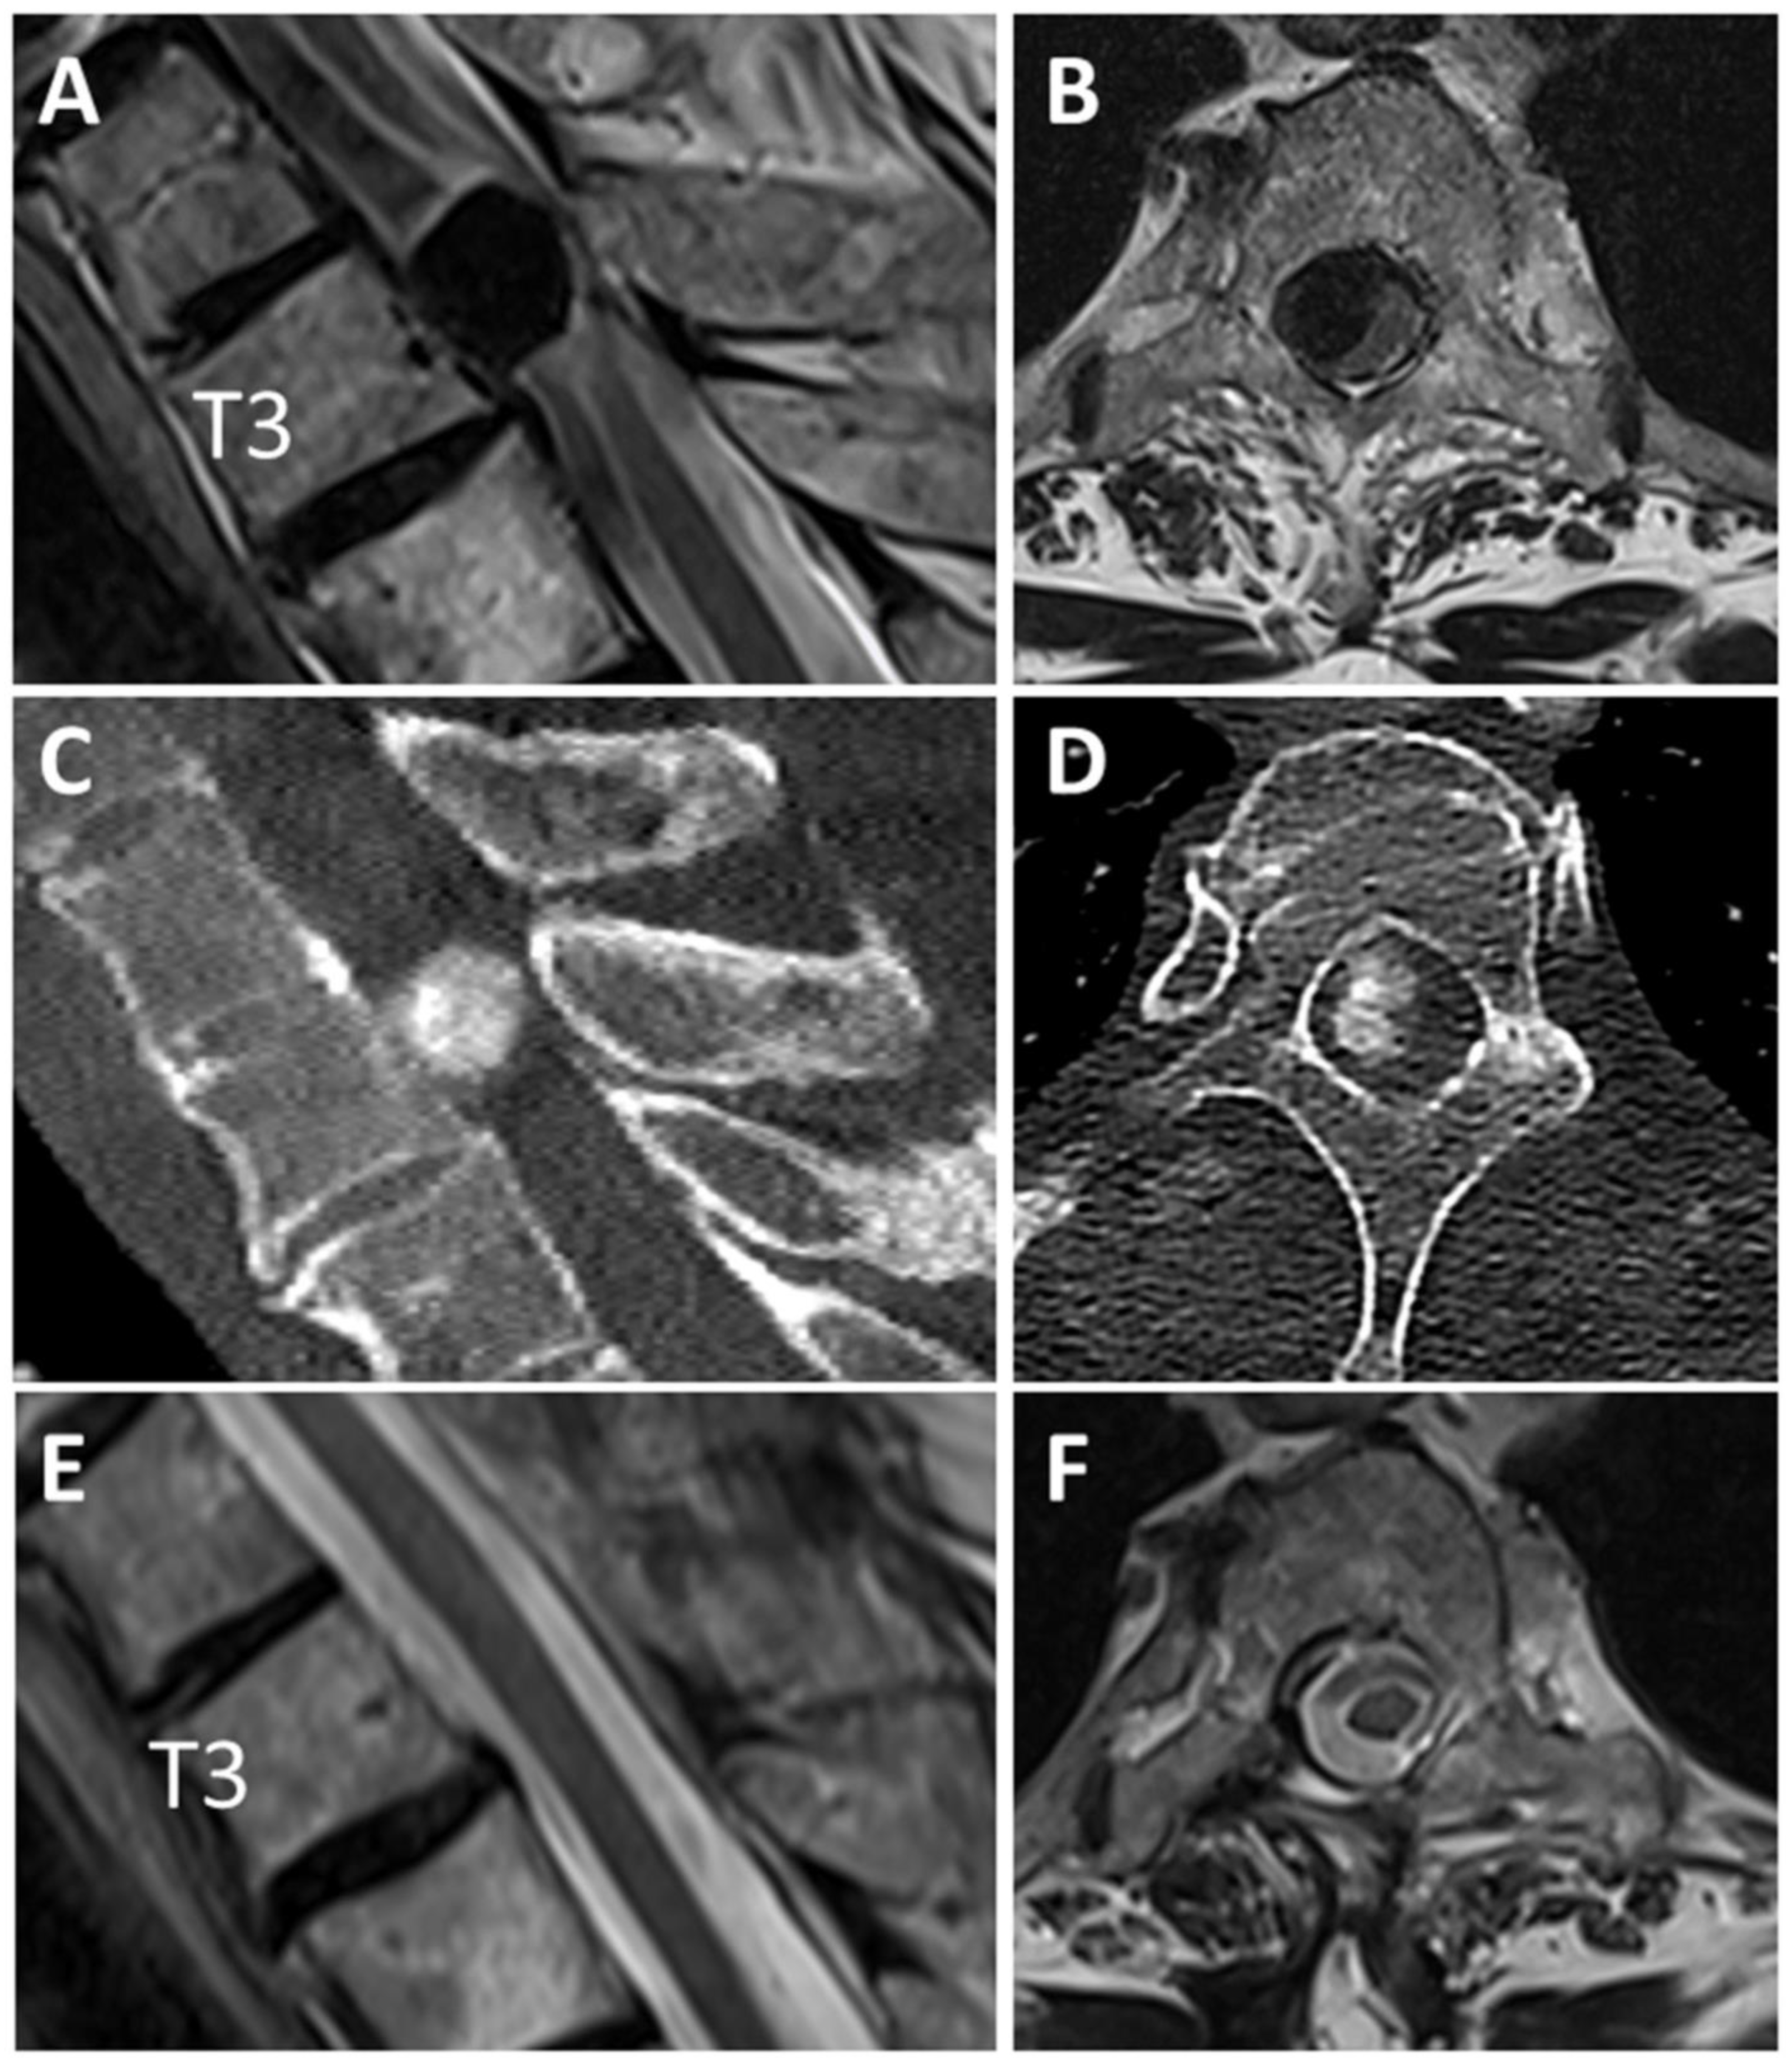

Descriptive Case

- Thakur, J.; Ulrich, C.T.; Schar, R.T.; Seidel, K.; Raabe, A.; Jesse, C.M. The surgical challenge of ossified ventrolateral spinal meningiomas: Tricks and pearls for managing large ossified meningiomas of the thoracic spine. J. Neurosurg. Spine 2021, 35, 516–526. [Google Scholar] [CrossRef] [PubMed]